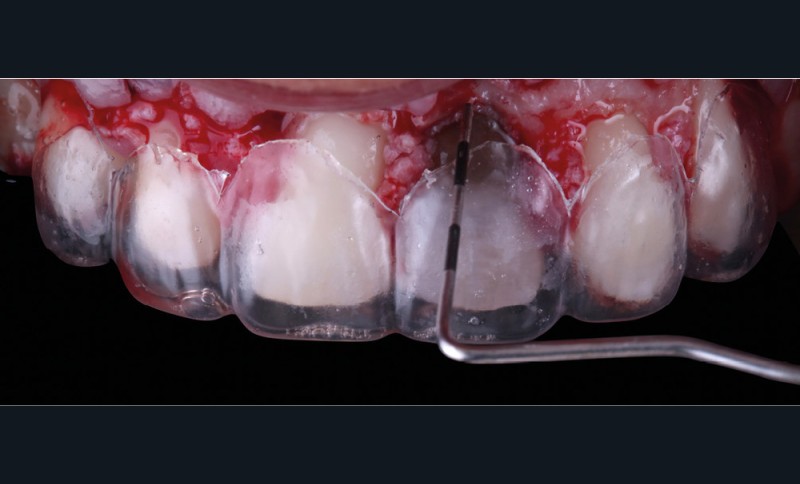

Acte 3 : gestion du rose soustractive (fig. 3 et 4)

Le laboratoire réalise d’abord un montage en cire (wax-up) à partir duquel une gouttière thermoformée sera préparée au cabinet. L’emplacement des futures dents, et surtout des futurs collets, est objectivé et nous guidera pour notre élongation coronaire. Cette chirurgie correctrice soustractive débute par une gingivectomie. Les collets une fois alignés, nous réalisons une ostéotomie/ostéoplastie. L’os vestibulaire est resséqué et positionné à 3 mm des futurs collets.